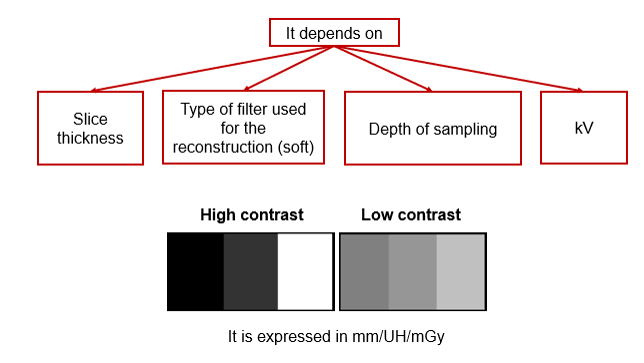

Contrast Resolution

Contrast resolution allows the differentiation of small structures depending on their densities.

Contrast resolution is measured in line pairs per centimeters. It is how it differentiates between two objects. There is high-contrast resolution, cross-plane resolution, and low contrast resolution.

Low contrast objects may require a larger pixel size so that the detectors can provide sufficient data for a visible difference but the total resolution is reduced.

The choice of x-ray tube voltage affects the image contrast. Low kV values mean higher contrast or few shades of gray, more black and white, while high kV values are selected when acquiring images with low contrast or one that requires seeing many shades of gray.

CR and Slice Thickness

These images demonstrate that the thicker the slice, the lower the contrast resolution. Although in general, an image with a thicker slice contains more x-ray photons (or less noise), the partial volume effect can reduce the visibility of smaller objects.